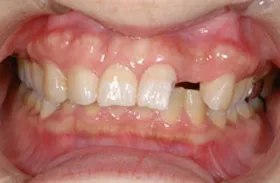

生まれつき歯が生えてこなかったケース

■治療前:生まれつき下顎左右前歯がなく隙間がある

■治療後:矯正治療後、下顎左右3番の2本にインプラント治療

| 主訴 | 生まれつき歯がなく隙間があり、審美障害・咀嚼機能障害がある |

| 治療方法 | インプラント治療 + 矯正治療 |

| 治療期間 | インプラント治療 約6ヶ月 |

| 通院回数等 | インプラント治療 約6回 |

| 費用 | 約94万円(税込) |

| リスク・副作用 | 術後の腫れ・痛み |